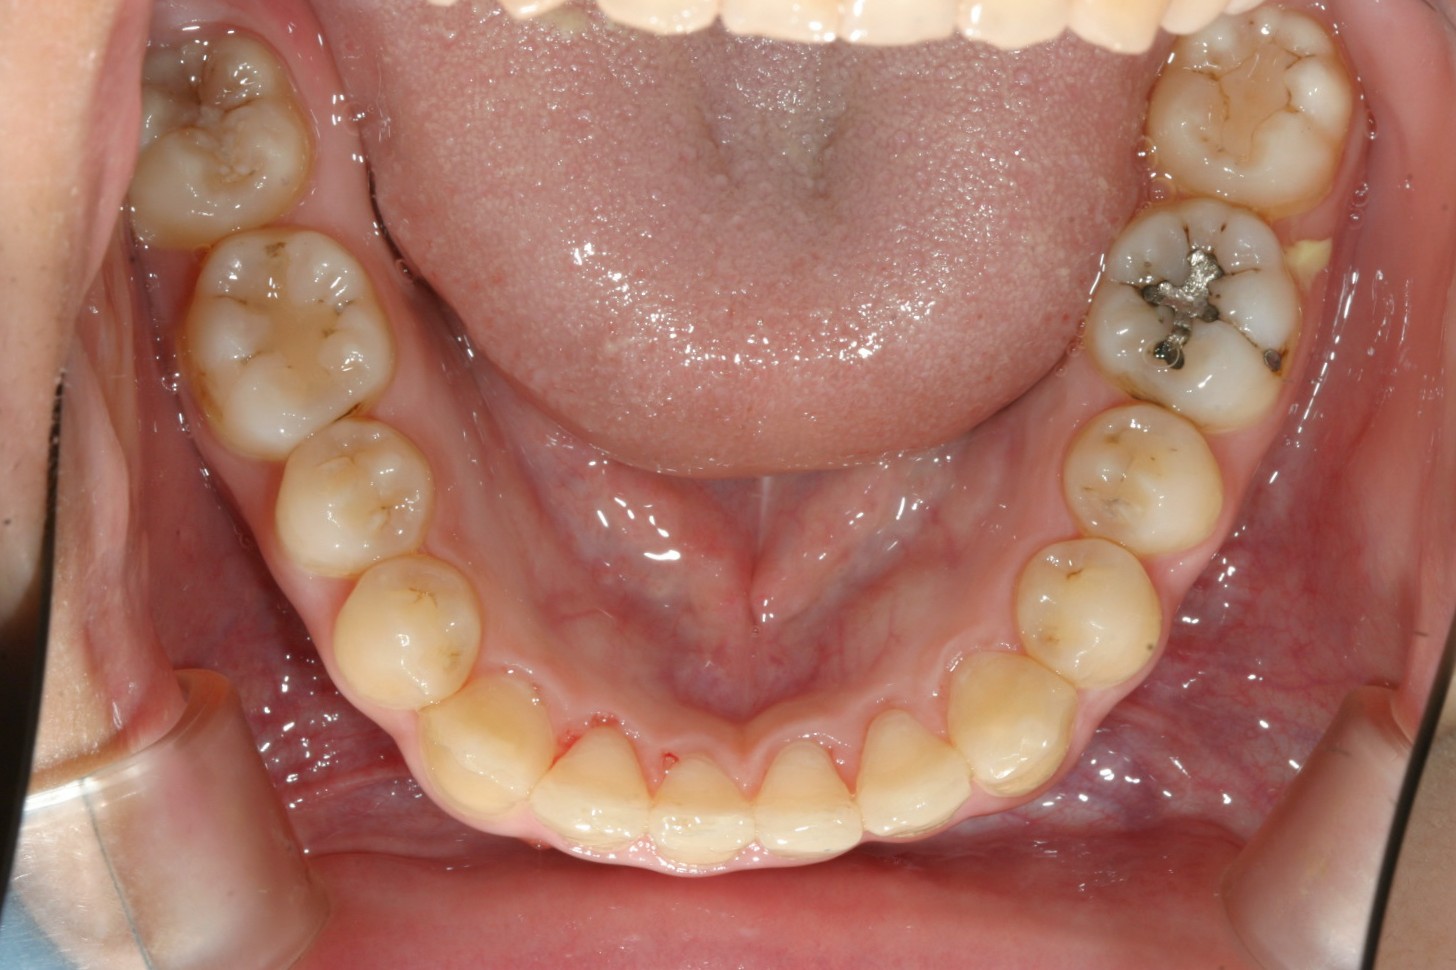

上顎は綺麗なアーチに改善されました。

下顎も綺麗なアーチになっています。